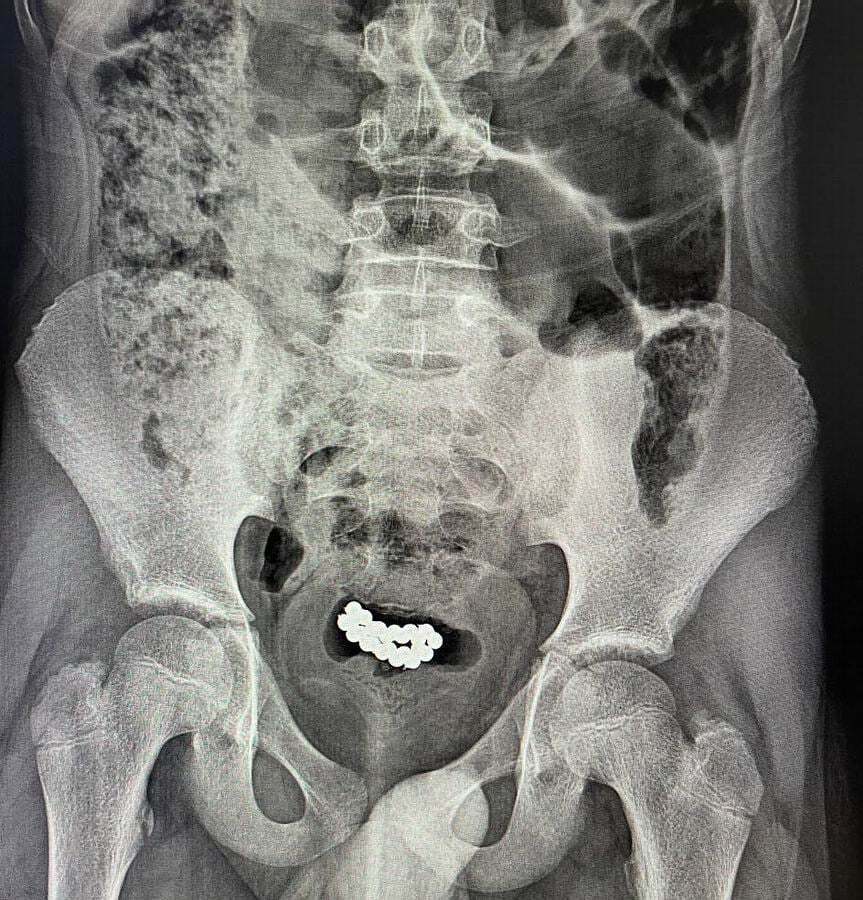

В Волынской области двое подростков попали в больницу с десятками магнитных шаров в мочевых пузырях. Предметы попали в организм юношей через отверстие уретры. Подростков пришлось оперировать.

Речь идет о подростках 10-15 лет. Как рассказали в медицинском учреждении 62 и 24 магнитных шарика были изъяты из мочевых пузырей парней.

"В обоих случаях была выполнена цистотомия мини-лапаротомным доступом с последующим извлечением 62 и 24 магнитных шариков", – сказано в сообщении. В учреждении добавили, что пациентов выписали из больницы в удовлетворительном состоянии, послеоперационный период у них прошел без осложнений.